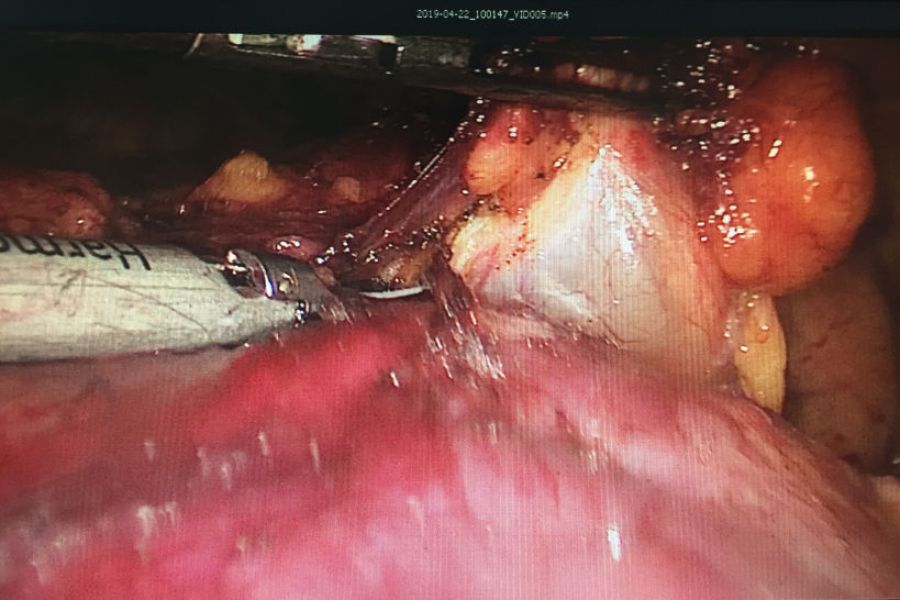

患者王某某40岁,因右胸阵发性疼痛1年入住我院疼痛科,检查发现前上纵膈肿瘤。经心胸外科钟强主治医师会诊后转入心胸外科。转入后予积极完善相关检查,排除相关禁忌症,考虑患者年轻,对创伤小、美观等要求,经研究决定予行胸腔手术。手术入路选择经剑突下切口,黄勇科主任及向加树副主任临场指导,术中杨智杰副主任医师、张建军主治医师及左选健住院医师密切配合,仔细解剖,历经2小时手术完整切除肿瘤。术后患者无明显并发症,主诉疼痛感轻,恢复良好。

纵膈肿瘤术中情况

经剑突下小切口VATS手术相对于侧胸切口VATS纵隔肿瘤手术具有暴露好的优点,但同时具有空间更小,难度更大,手术器械的相互干扰更大的特点,对手术者及助手的相关配合要求更高,经剑突下小切口VATS手术的顺利完成标志着心胸外科微创手术技术已步入成熟稳定发展期。